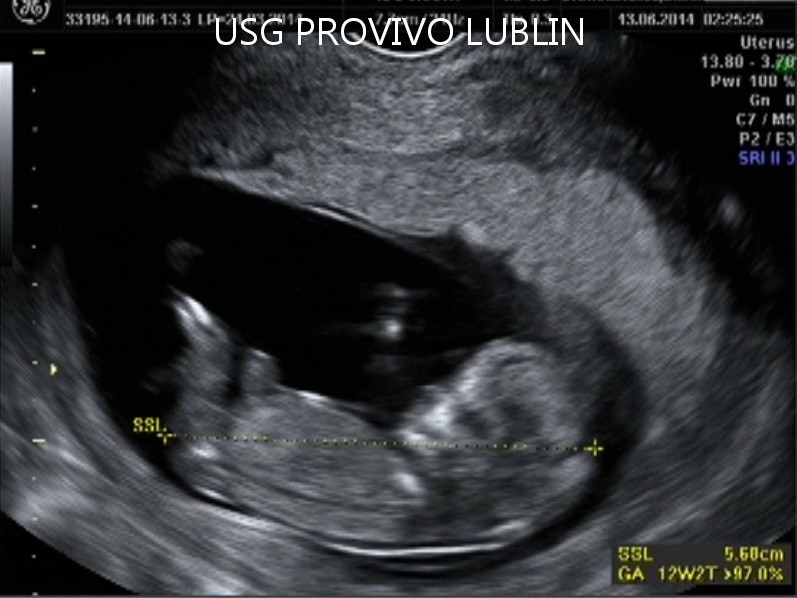

BADANIE USG 3/4D umożliwa dokładny wgląd w rozwój płodu, pozwala na podglądnięcie dziecka w sposób niemalże identyczny z jego aktualnym wyglądem.